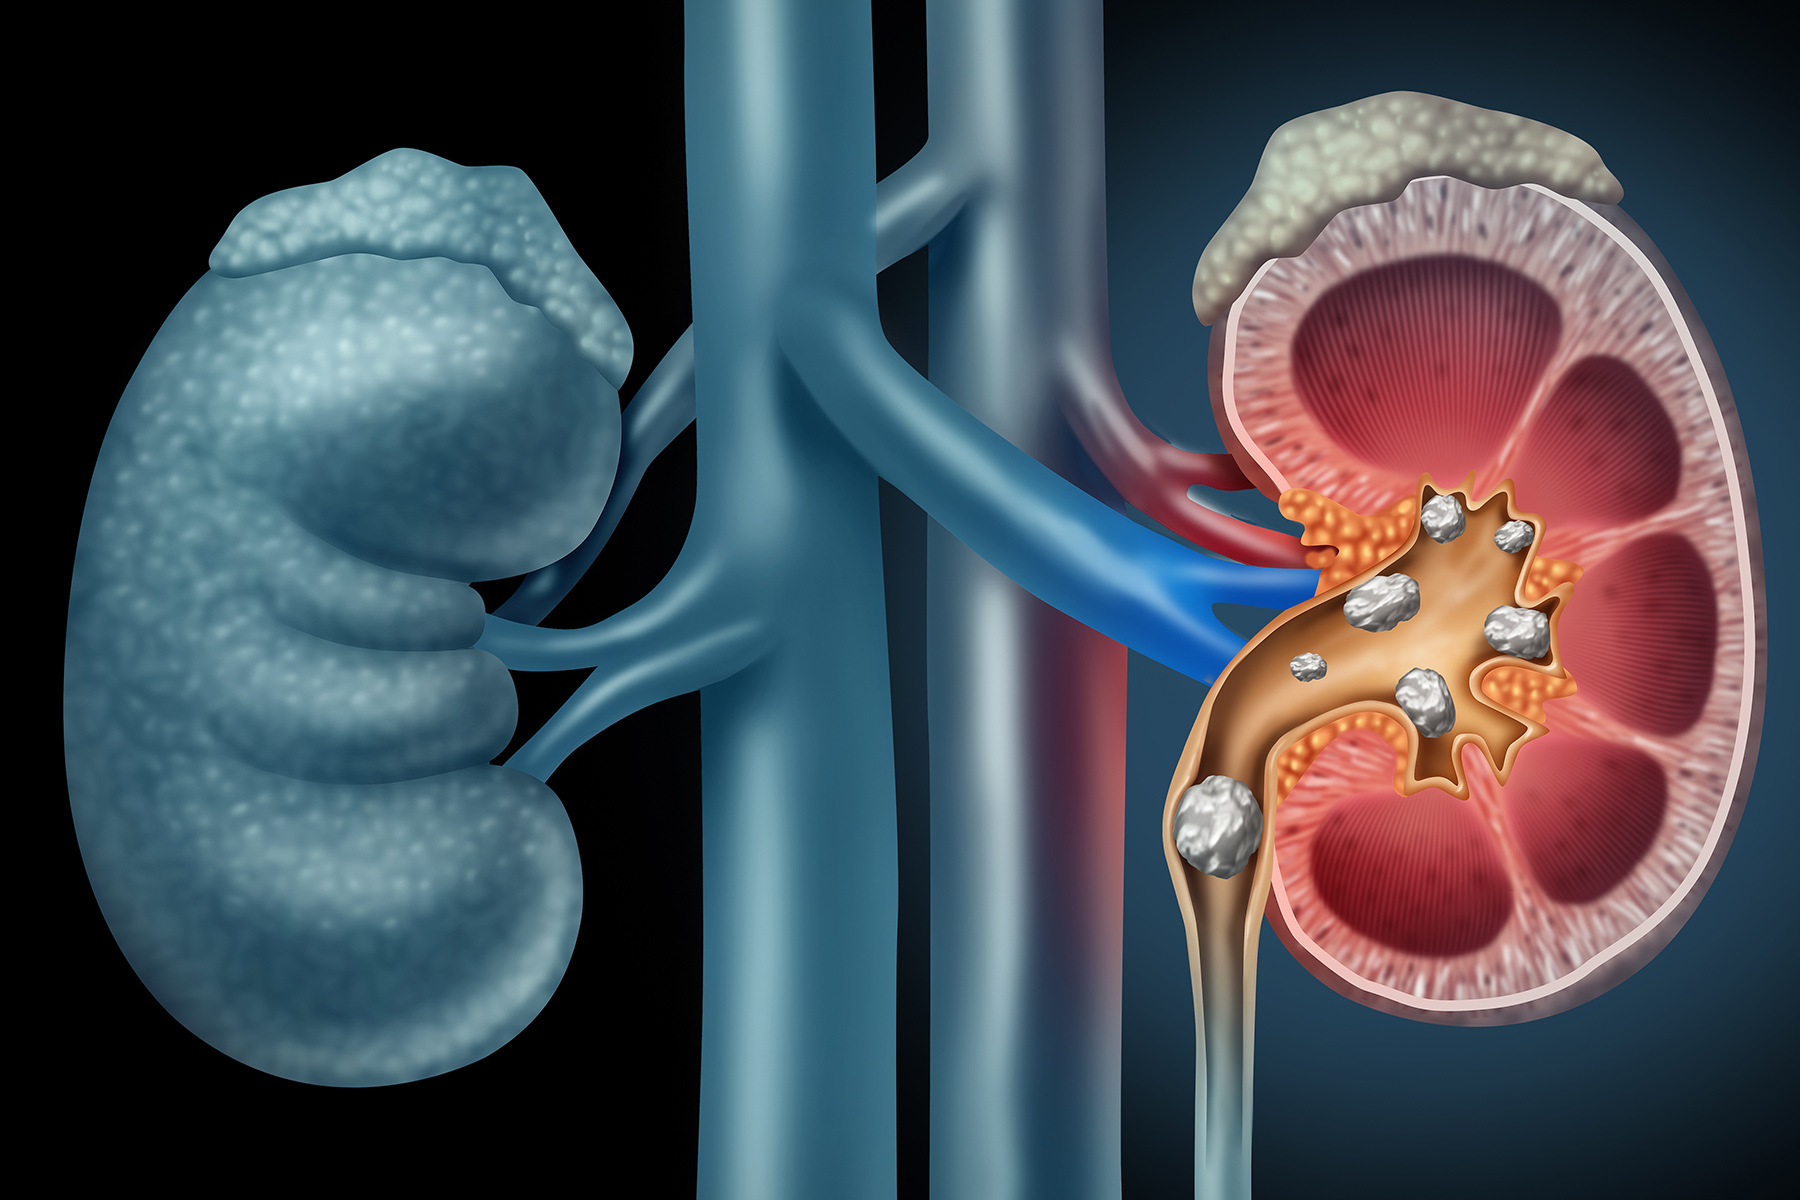

肾结石

矿物质和盐分在肾脏中形成微小石块。通常会觉得自己老想去洗手间,但尿尿并不多。可能会出现恶心,发烧,发冷和身体背部的一侧会严重疼痛,像波浪一样延伸到腹股沟。肥胖,脱水,高蛋白饮食和有家族病史的人患肾结石的可能性更高。结石可能会自行脱落,或者可能需要进行手术。